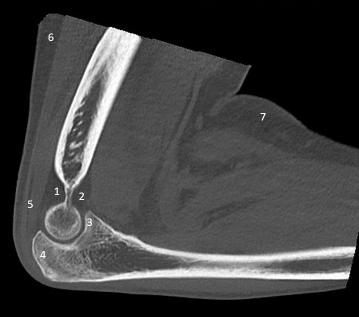

1 / 10

1. Observe a imagem acima. Que estrutura está rotulada com o número 2?

2 / 10

2. Observe esta imagem. Que estrutura corresponde ao número 5?